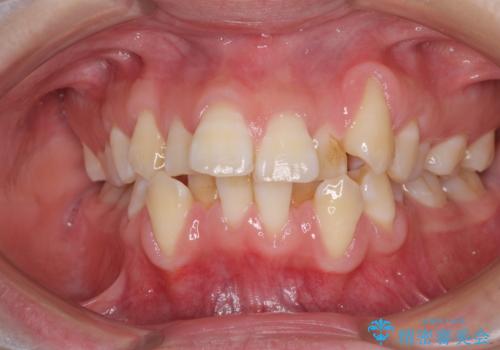

- 上下前歯の叢生と八重歯を気にして来院された患者様です。

前歯部叢生のスペースを獲得するため、上下顎左右小臼歯各1歯を抜歯することとしました。